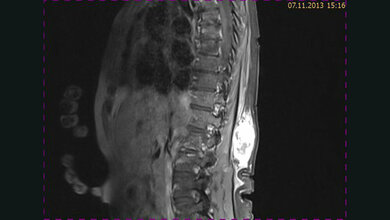

Ein moderner 1.5-Tesla-Magnetresonanztomograph

Die Hyperthermie-Einheit der Medizinischen Klinik III ist mit 3 Hyperthermiesystemen für die Behandlung von Tumoren im Bereich des Abdomens/Beckens sowie der Extremitäten von Erwachsenen und Kindern sowie einem System für die Behandlung von oberflächlichen Tumoren ausgestattet. Durch die Integration eines modernen 1.5-Tesla-Magnetresonanztomographen kann zusätzlich eine dreidimensionale Temperaturüberwachung durchgeführt werden.